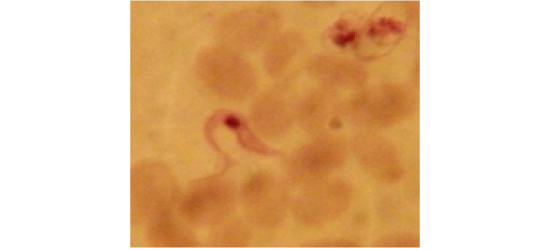

Showing short stumpy form of T. evansi in examined camel (x 1000).